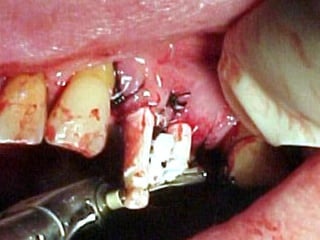

Primer tiempo quirúrgico; Exposición del maxilar para tomar una impresión del

hueso y poder elaborar la estructura implantaria.

Exposición del maxilar para tomar la impresión

Previamente se ha elaborado un portaimpresiones en acrílico de autopolimerización, el

cual será llenado con silicona para obtener el duplicado de la estructura ósea.

En el modelo que se obtuvo en el primer tiempo quirúrgico se elabora en el

laboratorio la estructura que se adptará al maxilar por mecanismo de grapa.

Segundo tiempo quirúrgico para aplicar la estructura.

Estructura en íntimo contacto con la superficie ósea, quedando los postes

fuera de la fibromucosa gingival..

Sutura de colgajos que cubren la estructura, dejando los postes bien visibles.

Colocación de la prótesis dentaria.

Primer tiempo quirúrgico;Exposición del maxilar para tomar una impresión del hueso y poder elaborar la estructura implantaria.

Exposición del maxilarpara tomar la impresión

Previamente se haelaborado un portaimpresiones en acrílico de autopolimerización, el cual será llenado con silicona para obtener el duplicado de la estructura ósea.

En el modeloque se obtuvo en el primer tiempo quirúrgico se elabora en el laboratorio la estructura que se adptará al maxilar por mecanismo de grapa.

Segundo tiempo quirúrgicopara aplicar la estructura.

Estructura en íntimocontacto con la superficie ósea, quedando los postes fuera de la fibromucosa gingival..

Sutura de colgajosque cubren la estructura, dejando los postes bien visibles.

Colocación de laprótesis dentaria.